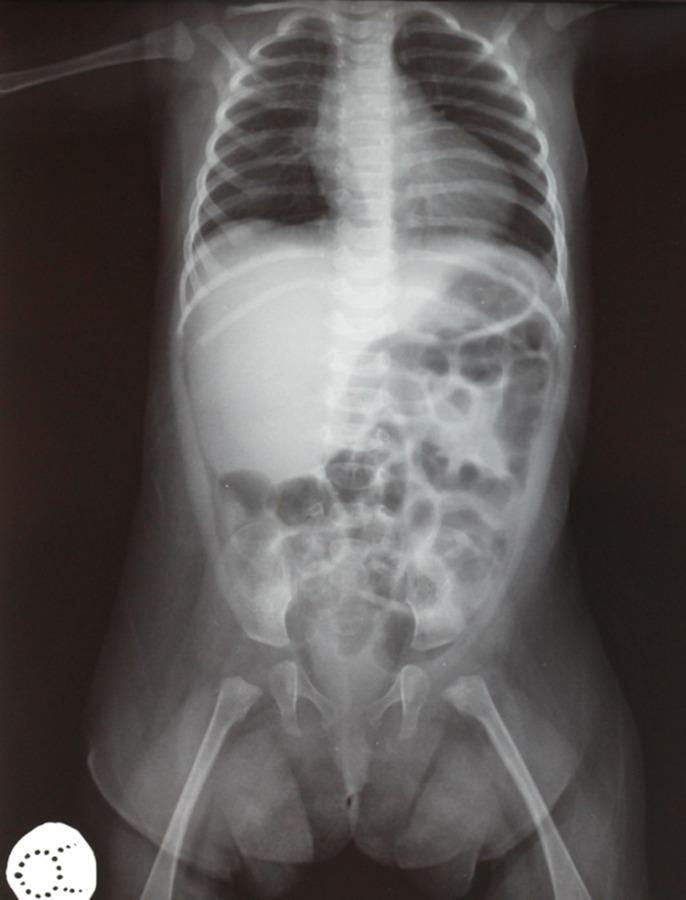

Majewski osteodysplastic primordial dwarfism type II (MOPD II) is an unusual autosomal recessive inherited form of primordial dwarfism, which is characterized by a small head diameter at birth, but which also progresses to severe microcephaly, progressive bony dysplasia, and characteristic facies and personality. This report presents a case of a five-year-old girl with MOPD II syndrome. The patient was referred to our clinic with the complaint of severe tooth pain at the left mandibular primary molar teeth. Clinical examination revealed that most of the primary teeth had been decayed and all primary teeth were hypoplastic. Patient's history revealed delayed development in the primary dentition and radiographic examination showed rootless primary molar teeth and short-rooted incisors. The treatment was not possible due to the lack of root of the left mandibular primary molars; so the teeth were extracted. Thorough and timely dental evaluation is crucial for the prevention of dental problems and the maintenance of oral health in patients with MOPD II syndrome is of utmost importance.

II型马耶夫斯基骨发育异常原发性侏儒症(MOPD II)是一种罕见的常染色体隐性遗传的原发性侏儒症,其特征是出生时头径小,但也会发展为严重的小头畸形、进行性骨发育异常以及特征性面容和性格。本报告介绍了一名患有MOPD II综合征的5岁女孩的病例。该患者因左侧下颌乳磨牙严重牙痛前来我院就诊。临床检查发现大多数乳牙已龋坏,所有乳牙均发育不全。患者病史显示乳牙列发育延迟,影像学检查显示乳磨牙无根,切牙牙根短。由于左侧下颌乳磨牙无根,无法进行治疗,因此拔除了牙齿。全面及时的牙科评估对于预防牙科问题至关重要,维护MOPD II综合征患者的口腔健康至关重要。